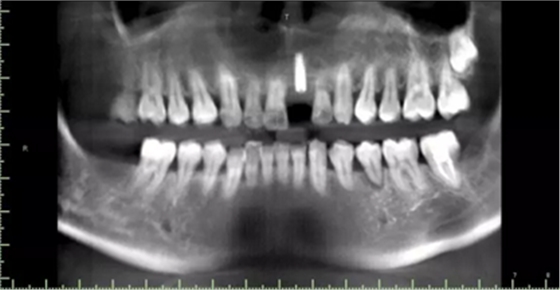

術(shù)前檢查

1.術(shù)前CT